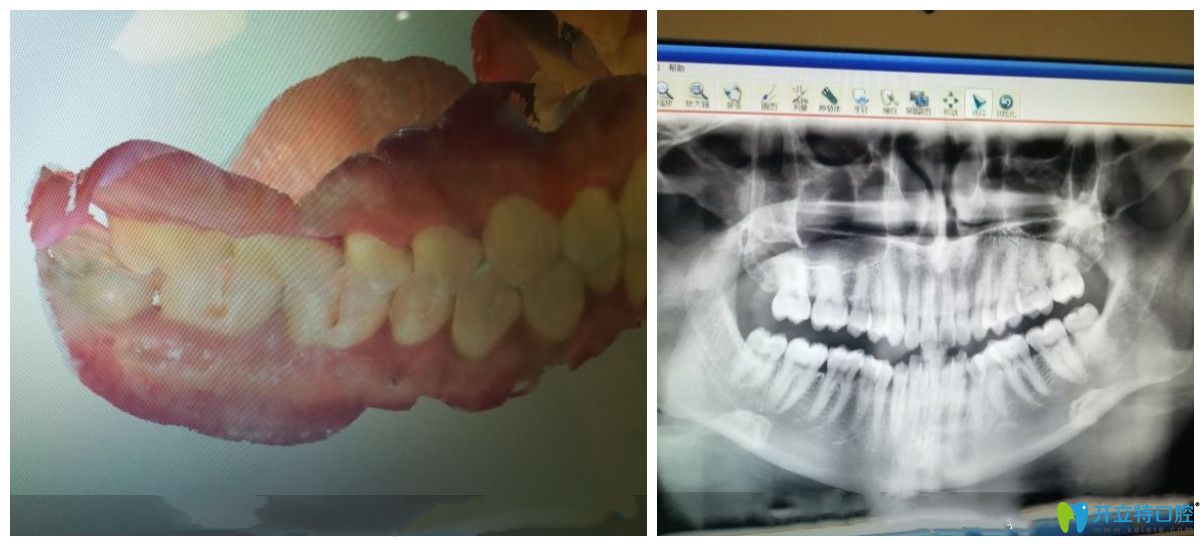

在成都圣貝口腔做隱形矯正前檢查圖

【顧客文字評(píng)價(jià)】:看到朋友在這里做的矯正還挺好的,就來檢查一下。之前也對(duì)比了好幾家,感覺這邊的醫(yī)生更專業(yè)更細(xì)心些。感還是蠻不錯(cuò)的,我的朋友做的粘釘?shù)模矣X得不好看就想做隱形的。聽方案的時(shí)候很明顯的感覺到和其他的醫(yī)生講方案不同,完全是從我的角度進(jìn)行推薦。